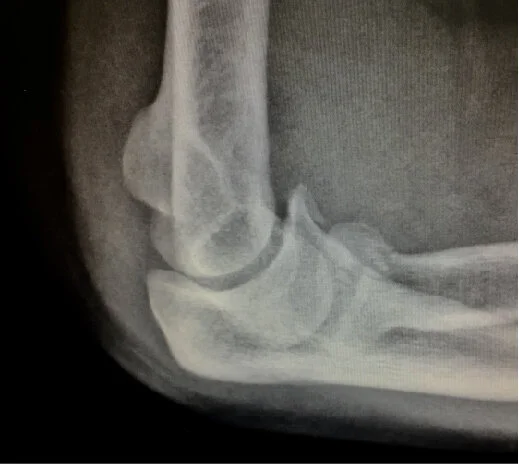

The patient fell onto her dominant arm, sustaining a displaced and impacted radial head fracture, along with a non-displaced coronoid fracture. She was seen in an ER and treated with a sling, and presented to my office 3 days after her injury. She had already regained a reasonable arc of elbow flexion/extension, but had a mechanical block to forearm rotation. Her injury films are shown below.

The patient was placed in the supine position utilizing the ElbowLOC® Arm Positioning System. Double anterolateral and standard anteromedial portals were established. A small elevator was utilized to reduce the radial head fracture, then screws were inserted through one of the lateral portal incisions, manipulating the forearm as needed. The coronoid fracture was non-displaced and stable on arthroscopic exam and was treated conservatively. The collateral ligaments were intact. Intraoperative arthroscopic photos and four month post op X-rays are below. The patient wore a sling for comfort postoperatively, and began supervised physical therapy 2 weeks post op. Four months post-op, she had no pain, full forearm rotation, a 5 degree flexion contracture and flexion to 140 degrees.